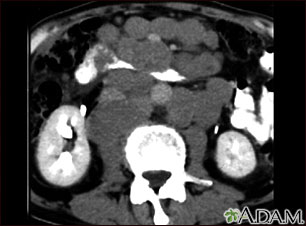

This abdominal CT scan shows tumor masses (malignant lymphomas) in the area behind the peritoneal cavity (retroperitoneal space).